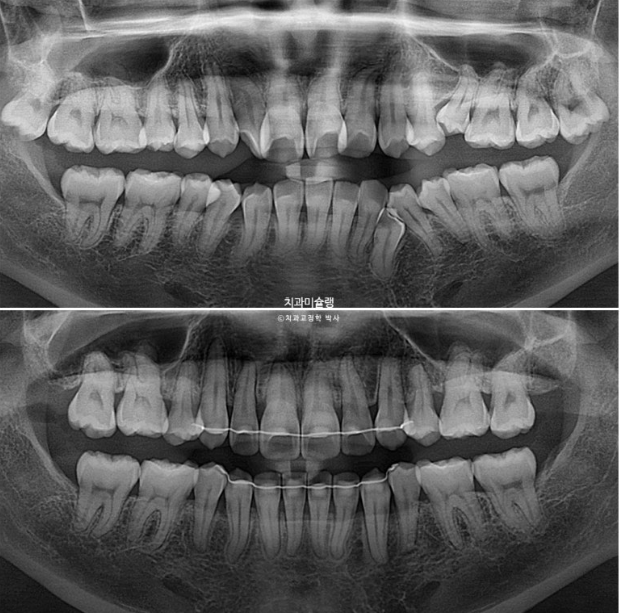

24.12

엑스레이에서 보이듯 이미 쓰러진 일부 어금니들을 세우고

미세하게 남은 발치공간을 닫고 교합을 안정화 시키고자 재제작에 들어갑니다.

어금니 쓰러진 부분들은 추가장치로 다시 세워 치근평행도는 좋습니다.

발치공간이 치실 헐겁게 들어갈 정도가 아직 남았고 구치부 교합도 좀 더 개선하고자 2번째 재제작에 들어갑니다.

23.10~26.01

2년 3개월의 치료기간동안 치근흡수는 없고 치근평행도는 양호합니다.